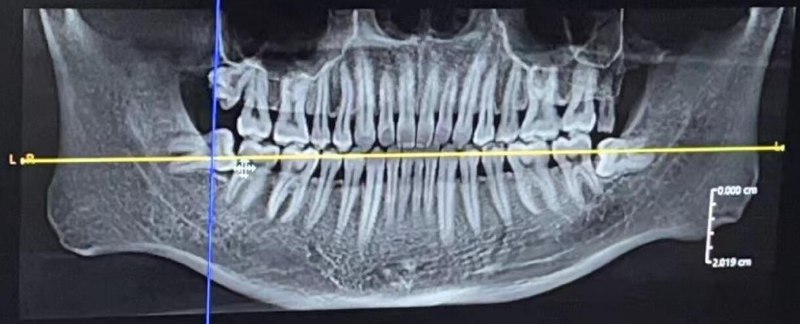

周末终于去拔了智齿

brader: 医生技术真好,先拔左边两颗,打完麻药开始拔,几分钟就给我搞定了。

3 颗牙(下面 2 颗,左上 1 颗),朋友介绍的给我打 85 折,报完医保最后自费 2015.7 ,大家觉得贵吗?